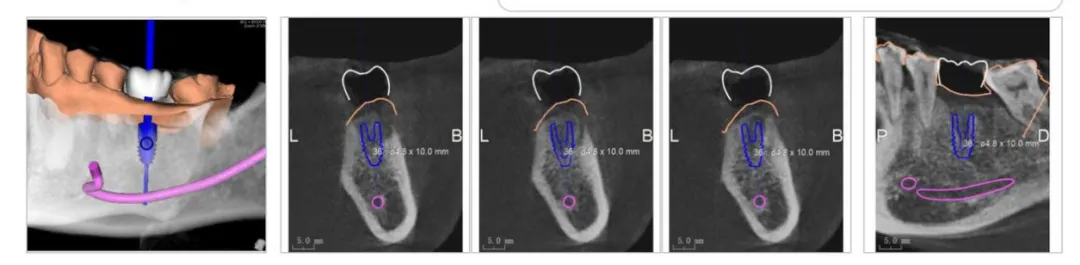

患者骨密度图像

海德堡联合口腔的种植牙概念一直是以修复为导向,依靠德国全数字化微创种植技术,可以明确的标示出神经与血管的位置,根据每一个人每一颗牙齿的骨质分析,精确模拟出种植体种植的方向、角度、深度,将各种数据精准的控制在安全范围内。

可以极大的避免种植体在骨头里边的松动,保证取得一个好的骨结合的结果。

数字化种植方案标识出神经、血管、种植体的位置

在德国全数字化种植技术的引导下,可以将种植手术的精准度、高效性、微创性瞬间提升,毕竟“创伤越小,术后的风险越低”。

胡阿姨缺失左上5号牙,右下6号牙,骨3类,属于骨质情况中度良好的情况。所以为其选择数字化微创导板种植方案。

此次手术,李志峰院长为胡阿姨做右下6号牙的种植。“因为6号牙属于主要功能牙,缺失会影响到咀嚼。”

患者术前方案细节图